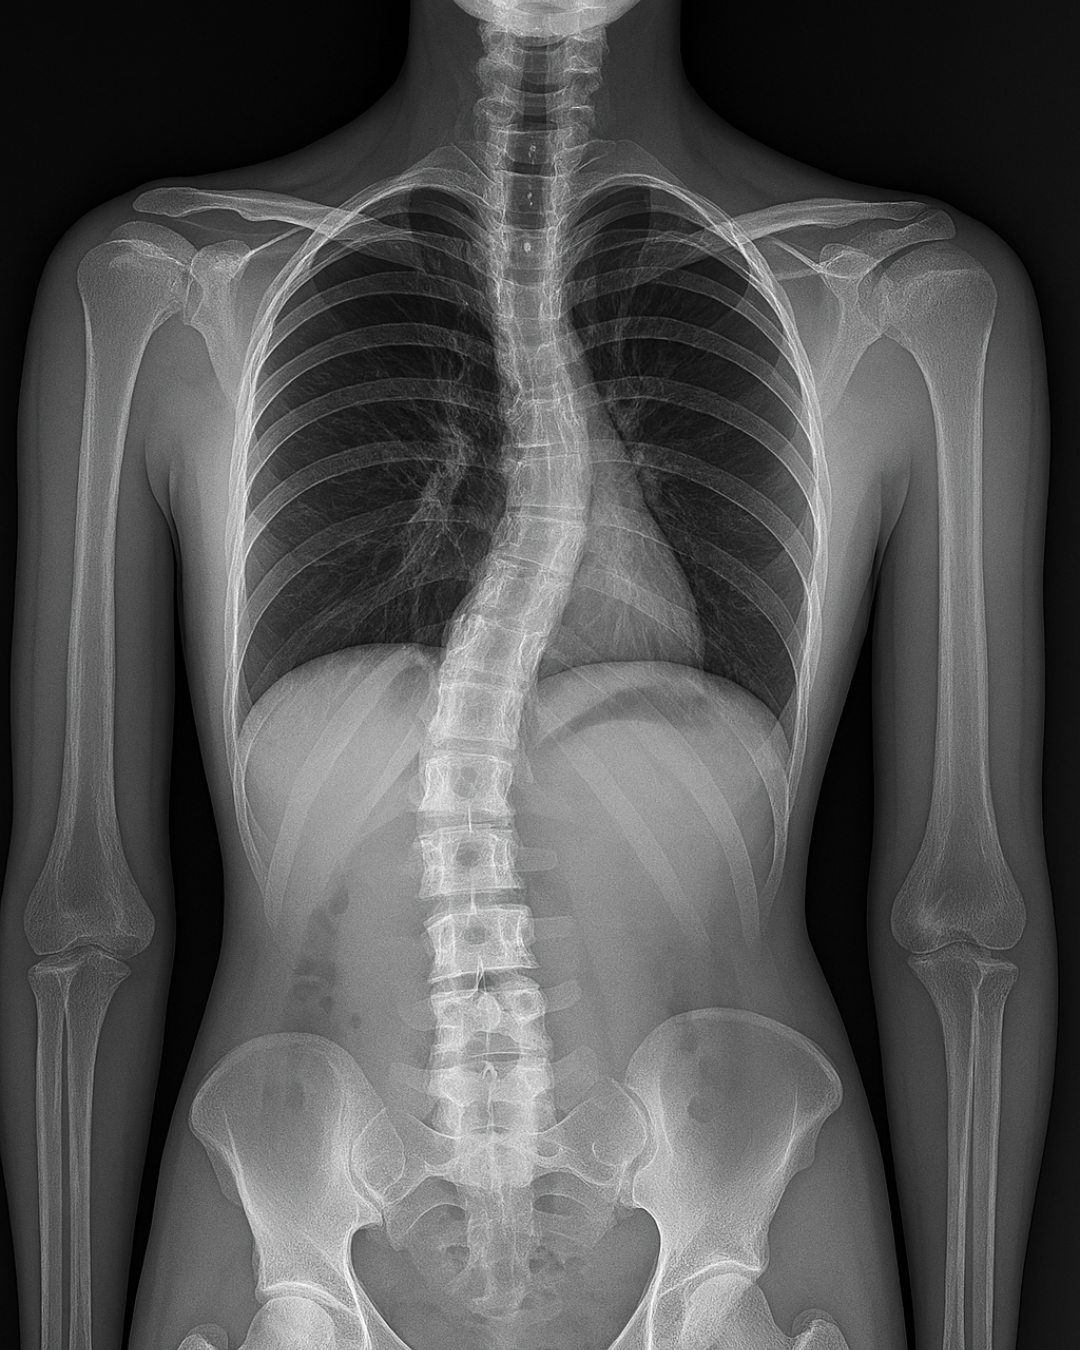

This private research study is exploring a potential new approach to spinal movement awareness for adolescents with idiopathic scoliosis. Participants will receive guided instruction on how to focus on and move individual parts of the spine in a safe, supportive setting.

Girls ages 12–14 years with idiopathic scoliosis (Cobb angle 30° or less) who are in good general health and have no history of spinal surgery. Participants should be able to take part in gentle movement sessions.